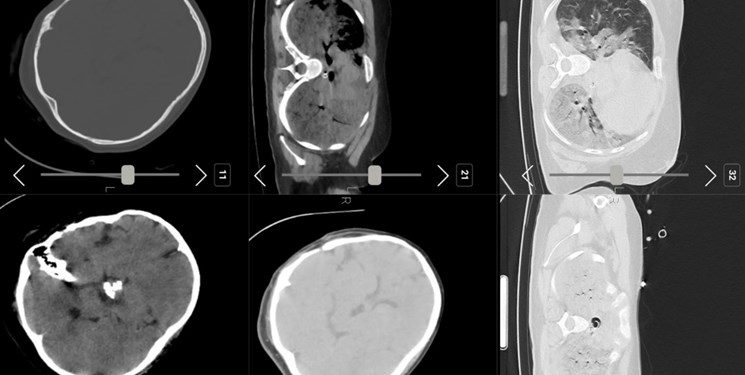

وی با بیان اینکه ضربه مغزی که بتواند باعث مرگ فرد شود با خون‌ریزی یا سایر علایم مرتبط همراه است گفت: هیچ نشانی از موارد ذکر شده در سی تی اسکن‌های بیمار مشاهده نشده است. مردم جامعه حق دارند که با این سوال مواجه شوند که چرا یک شخص جوان بدون ضربه مغزی جان باخته است؟ این سوال برای پزشکان نیز به وجود آمده بود اما بررسی سی‌تی اسکن و پرونده بیمار نشان می‌دهد مهسا امینی در بیمارستان میلاد جراحی مغز انجام داده است و همه تصاویر نشان می‌دهد باز کردن جمجمه بیمار از سمت راست مغز برای خارج کردن تومور جراحی انجام شده است و آثار جراحی روی جمجمه مشهود است؛ همچنین قسمتی از تومور نیز در مغز بیمار باقی مانده است.

قناعتی توضیح داد: بررسی‌ها نشان می‌دهد بیمار به دلیل انجام این جراحی به دیابت بی‌مزه نیز مبتلا بوده است.نظرات تکمیلی ارایه خواهد شد. . پرونده بیمار باید توسط کمیته حقیقت یاب به صورت کامل بررسی شود تا حقی از خانواده بیمار تضییع نشود.